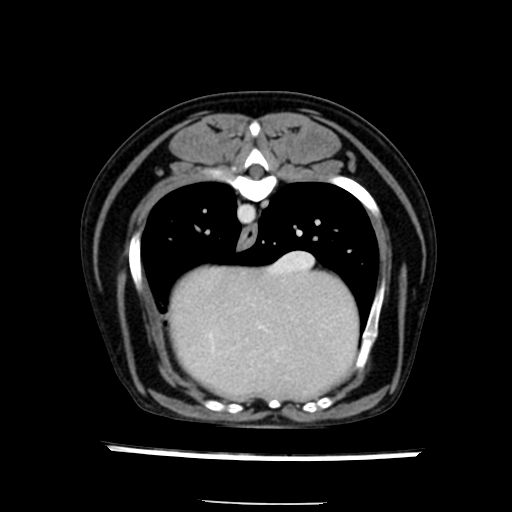

prescritto esame TAC

sequenza immagini limitata al fegato reni e surreni

le immagini ecografiche rispetto alla tac datano circa 7 mesi prima ,le surrenali sono normali nonostante il test acth sia risultato positivo .all’esame TAC dopo diversi mesi risultano aumentate armonicamente nel volume e si individua un forte sospetto di adenoma ipofisario .

sospetto adenoma ipofisario vs. meno probabilmente meningioma della base; intertiziopatia polmonare; lesione espansiva epatica, verosimilmente del lobo laterale sinistro, di sospetta natura neoplastica; lesioni spleniche di natura da definire; iperplasia/ipertrofia delle ghiandole surrenali, bilateralmente; vertebra di transizione del rachide toracico; tenosinovite cronica del muscolo bicipite brachiale di destra.